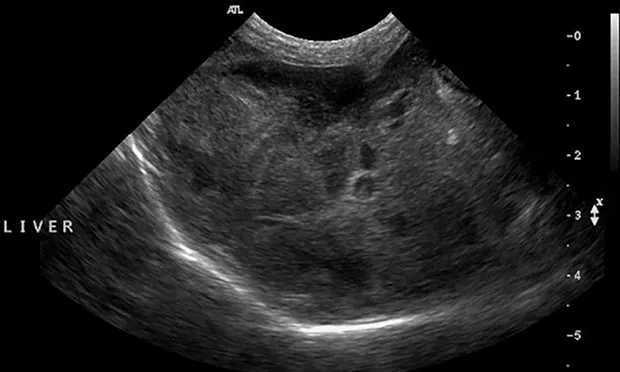

• Ultrasonography is generally the preferred diagnostic imaging modality for evaluation of the liver, and it is particularly useful for mucoceles.

• The normal liver has a homogenous echogenicity that is isoechoic to slightly hyperechoic to the renal cortex.

• Changes in hepatic echogenicity occur in acute and chronic liver disease (Figure 2).

• Ultrasonographic changes are usually not specific for a particular disease.

• The liver can also appear ultrasonographically normal, even in severe disease.

• Ultrasonography is useful for examination of the biliary system, including gallbladder size, contents, and wall thickness, as well as for the intra- and extra-hepatic bile ducts.

FIGURE 2 Ultrasonographic image demonstrating a diffusely mottled and nodular appearing hepatic parenchyma.